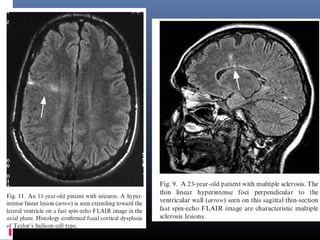

 Mesial temporal sclerosis: m/c pathology in patients with partial complex seizures.

Thin-section coronal FLAIR is the standard sequence in these patients & seen as a

bright small hippocampus on dark background of suppressed CSF-containing

spaces. However, normally also mesial temporal lobes have mildly increased SI on

FLAIR images.

 Focal cortical dysplasia of Taylor’s balloon cell type- markedly hyperintense

funnel-shaped subcortical zone tapering toward the lateral ventricle is the

characteristic FLAIR imaging finding

 In tuberous sclerosis- detection of hamartomatous lesions, is easier with FLAIR

than with PD or T2-W sequences